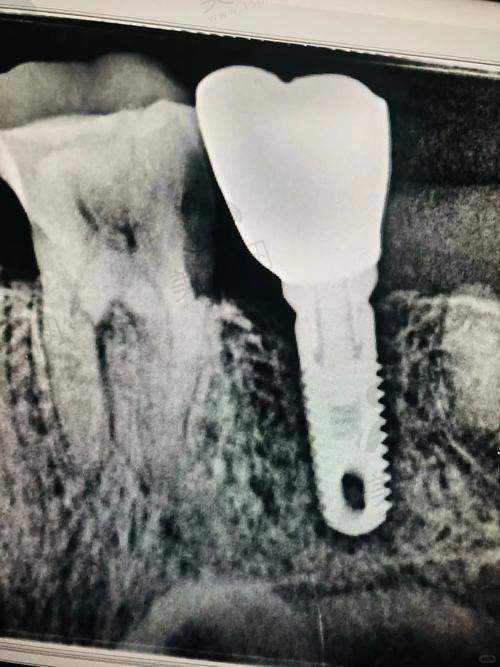

种植领域:掌握微创种植、即刻负重、ALL - ON - 4/6全口修复等核心技术,针对牙槽骨重度萎缩患者开展植骨术、上颌窦内外提升等复杂术式,使用瑞士ITI、德国ankylos、韩国奥齿泰等国内外一线种植系统,种植体5年存活率超99.2%。

常规种植:微创种植、即刻负重(单颗/多颗缺失),种植体品牌涵盖瑞士ITI、德国ankylos、韩国奥齿泰等。

2. 数字化种植导航系统:精细度达0.1mm

医院引进德国X - Guide动态导航种植技术,术前通过CBCT扫描构建三维口腔模型,术中实时引导种植体植入角度、深度,误差控制在0.1mm以内。针对半口/全口缺失患者,采用“即刻负重”技术,实现“当天种牙当天用”,较传统种植缩短3 - 6个月愈合周期。

成就:引进德国ankylos种植系统西南地区首批认证医师,年种植手术量超800台